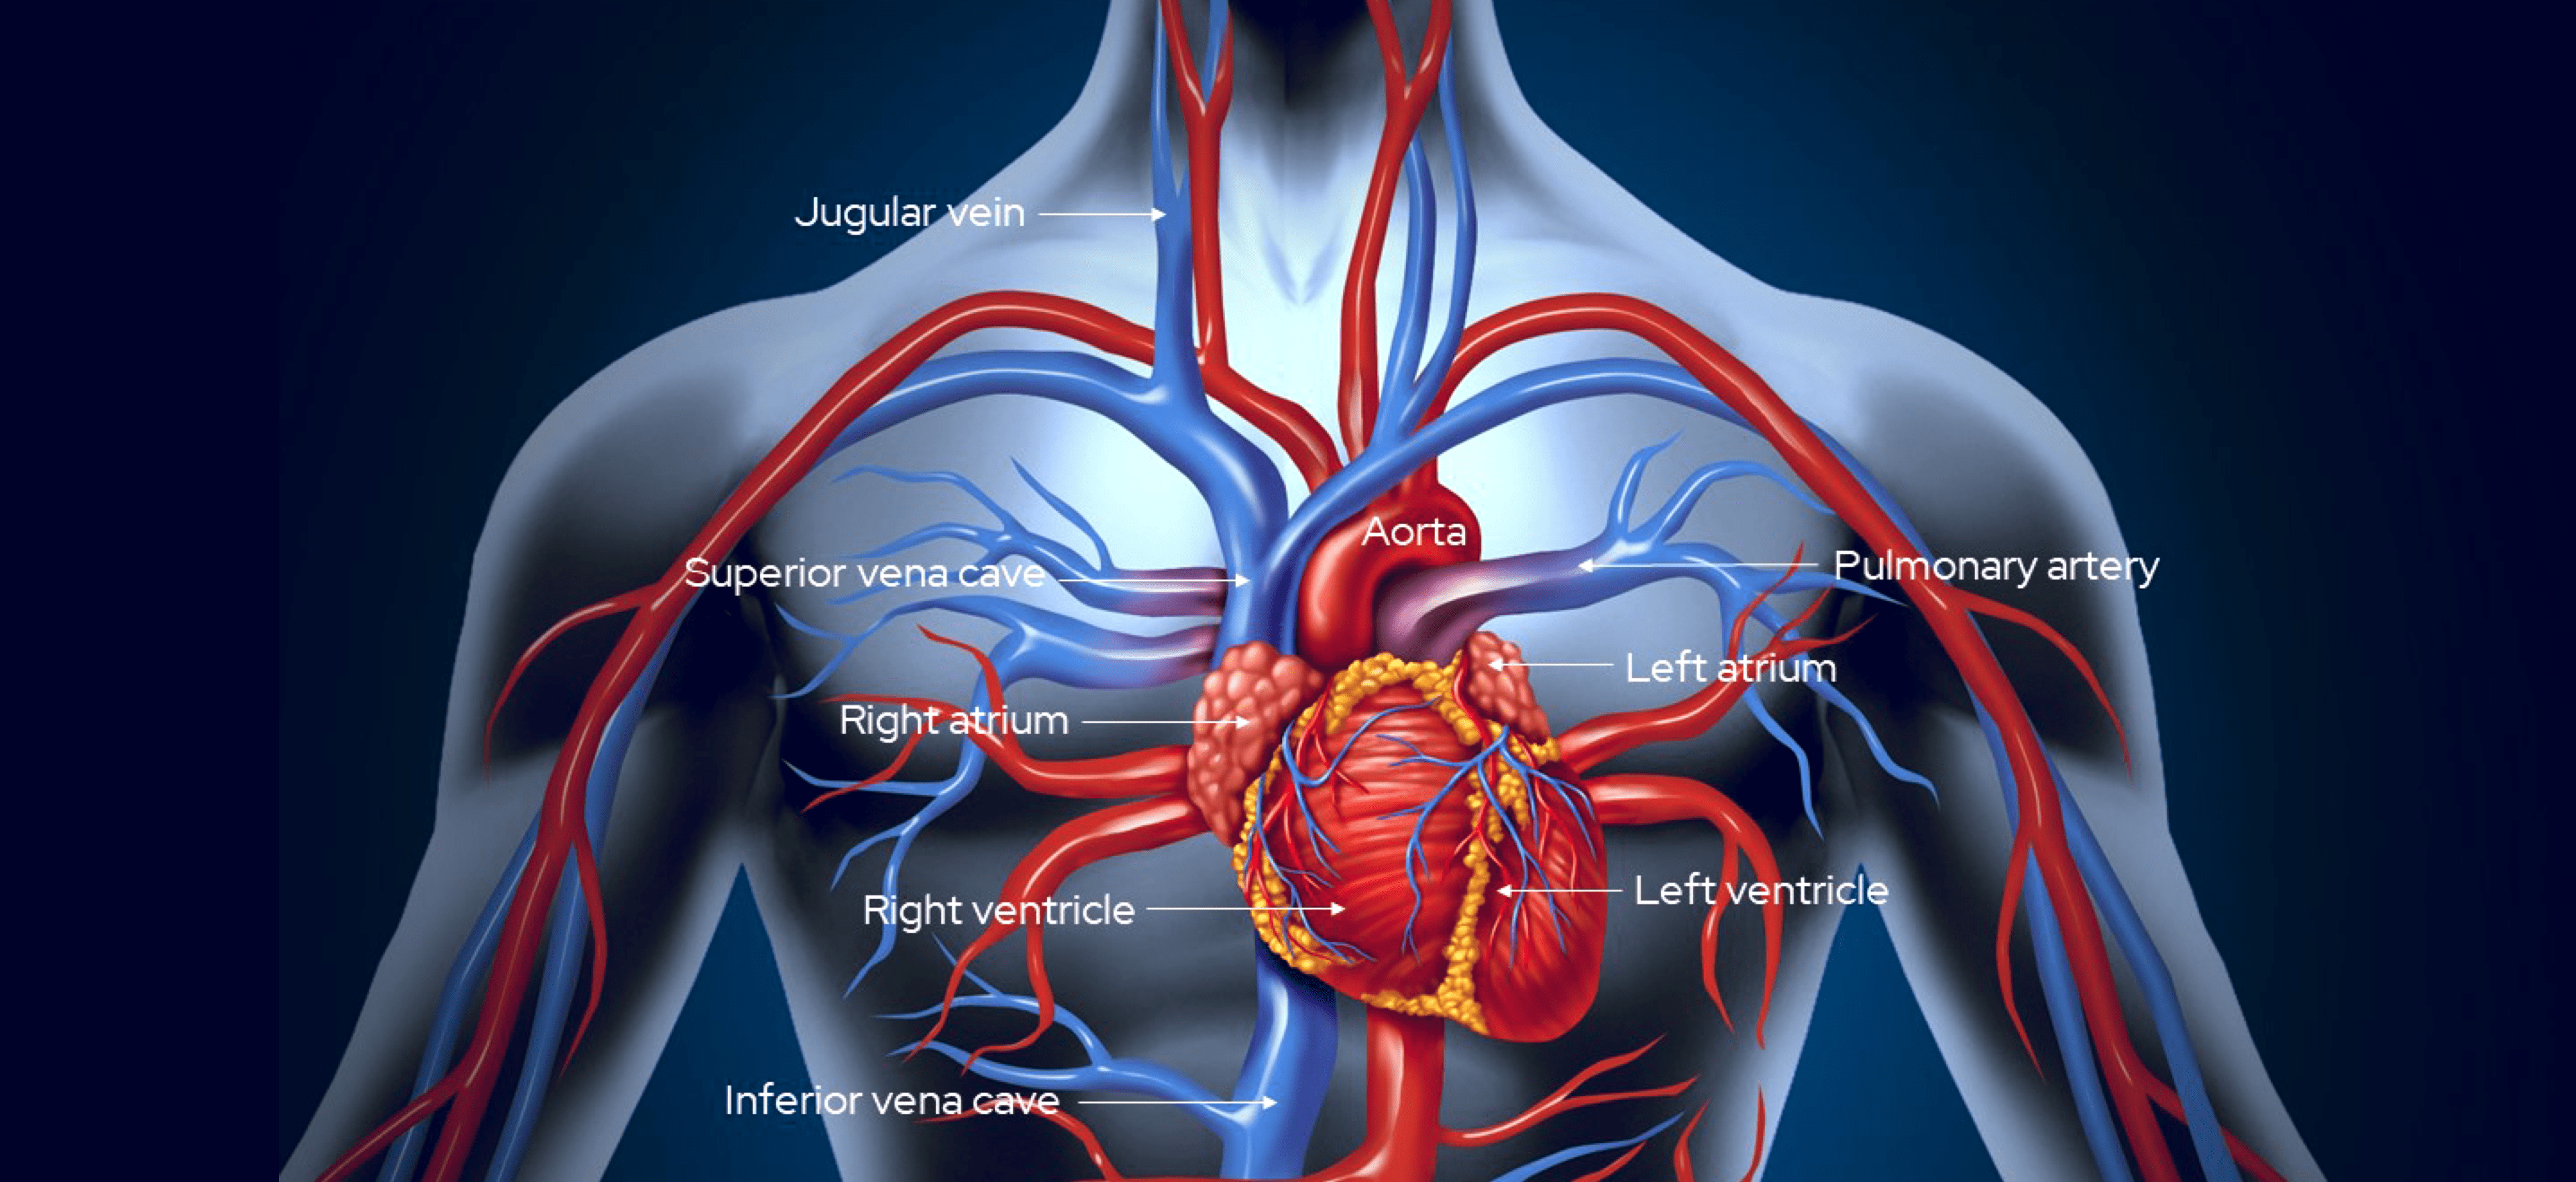

The aorta is the largest artery in the body. It carries the oxygenated blood directly from the left ventricle of the heart, and extends down to the abdomen, where it divides into smaller arteries, distributing oxygenated blood to the body.

Arteries are blood vessels that deliver oxygen-rich blood from the heart to the tissues of the body.

The heart is divided into four chambers. The two upper chambers are called atriums, and the two lower (larger) ones are called ventricles. The atriums prime the heart with blood to pump out to the body. The left atrium (LA) receives blood from the pulmonary vein, having been oxygenated by the lung. The right atrium (RA) receives unoxygenated blood from the vena cava (venous circulation – returning blood to the heart). Both atriums receive blood while relaxed (known as diastole). When the heart beats/contracts (known as systole) the blood is pumped from each atrium into its corresponding ventricle.

The carotid arteries are present on both the left and right sides of the body and are responsible for the supply of oxygenated blood to the head and neck. The average diameter of the carotid arteries in adults is 6.5mm (males) and 6.1mm (females).